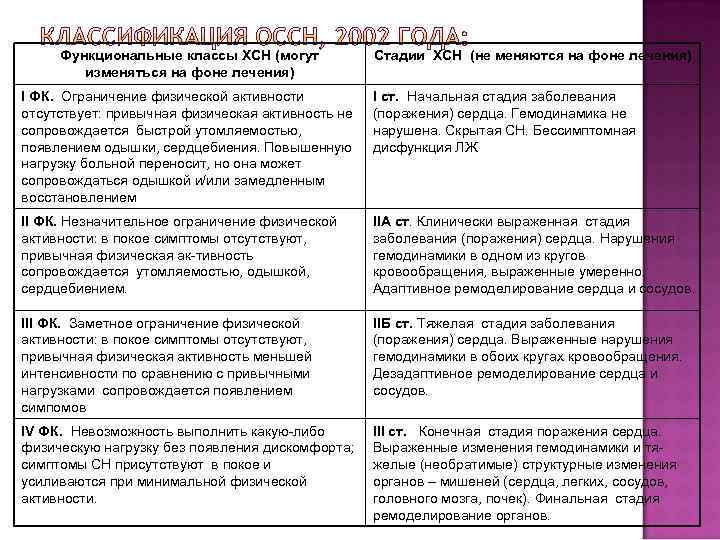

Функциональные классы ХСН (могут изменяться на фоне лечения) Стадии ХСН (не меняются на фоне лечения) I ФК. Ограничение физической активности отсутствует: привычная физическая активность не сопровождается быстрой утомляемостью, появлением одышки, сердцебиения. Повышенную нагрузку больной переносит, но она может сопровождаться одышкой и/или замедленным восстановлением I ст. Начальная стадия заболевания (поражения) сердца. Гемодинамика не нарушена. Скрытая СН. Бессимптомная дисфункция ЛЖ II ФК. Незначительное ограничение физической активности: в покое симптомы отсутствуют, привычная физическая ак-тивность сопровождается утомляемостью, одышкой, сердцебиением. IIА ст. Клинически выраженная стадия заболевания (поражения) сердца. Нарушения гемодинамики в одном из кругов кровообращения, выраженные умеренно. Адаптивное ремоделирование сердца и сосудов. III ФК. Заметное ограничение физической активности: в покое симптомы отсутствуют, привычная физическая активность меньшей интенсивности по сравнению с привычными нагрузками сопровождается появлением симпомов IIБ ст. Тяжелая стадия заболевания (поражения) сердца. Выраженные нарушения гемодинамики в обоих кругах кровообращения. Дезадаптивное ремоделирование сердца и сосудов. IV ФК. Невозможность выполнить какую-либо физическую нагрузку без появления дискомфорта; симптомы СН присутствуют в покое и усиливаются при минимальной физической активности. III ст. Конечная стадия поражения сердца. Выраженные изменения гемодинамики и тяжелые (необратимые) структурные изменения органов – мишеней (сердца, легких, сосудов, головного мозга, почек). Финальная стадия ремоделирование органов.

Функциональные классы ХСН (могут изменяться на фоне лечения) Стадии ХСН (не меняются на фоне лечения) I ФК. Ограничение физической активности отсутствует: привычная физическая активность не сопровождается быстрой утомляемостью, появлением одышки, сердцебиения. Повышенную нагрузку больной переносит, но она может сопровождаться одышкой и/или замедленным восстановлением I ст. Начальная стадия заболевания (поражения) сердца. Гемодинамика не нарушена. Скрытая СН. Бессимптомная дисфункция ЛЖ II ФК. Незначительное ограничение физической активности: в покое симптомы отсутствуют, привычная физическая ак-тивность сопровождается утомляемостью, одышкой, сердцебиением. IIА ст. Клинически выраженная стадия заболевания (поражения) сердца. Нарушения гемодинамики в одном из кругов кровообращения, выраженные умеренно. Адаптивное ремоделирование сердца и сосудов. III ФК. Заметное ограничение физической активности: в покое симптомы отсутствуют, привычная физическая активность меньшей интенсивности по сравнению с привычными нагрузками сопровождается появлением симпомов IIБ ст. Тяжелая стадия заболевания (поражения) сердца. Выраженные нарушения гемодинамики в обоих кругах кровообращения. Дезадаптивное ремоделирование сердца и сосудов. IV ФК. Невозможность выполнить какую-либо физическую нагрузку без появления дискомфорта; симптомы СН присутствуют в покое и усиливаются при минимальной физической активности. III ст. Конечная стадия поражения сердца. Выраженные изменения гемодинамики и тяжелые (необратимые) структурные изменения органов – мишеней (сердца, легких, сосудов, головного мозга, почек). Финальная стадия ремоделирование органов.